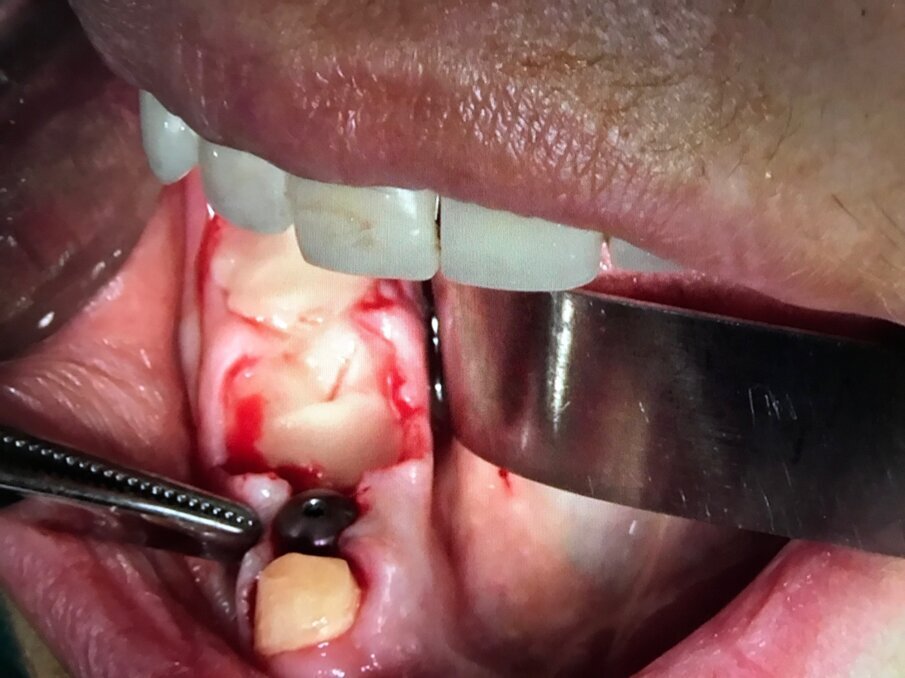

Infatti l’azione combinata su tessuti molli e su quelli duri, favorisce la rapida guarigione degli interventi chirurgici parodontali e delle tecniche additive ossee. Queste ultime devono essere predicibili, efficaci, sicure e poco costose soprattutto in relazione al fatto che tali tecniche spesso, sono finalizzate alla riabilitazione implantare e protesica delle arcate dentarie. In tal senso una tecnica che rende rapido e sicuro un ciclo riabilitativo implantoprotesico, diventa necessariamente una strategia terapeutica vincente. Diverse aziende implantari hanno sviluppato conoscenze scientifiche ed abilità commerciali in questo settore; a seguire la documentazione iconografica di una sequenza chirurgica in cui l’inserzione implantare e la rigenerazione ossea guidata sono supportate da I-PRF, utilizzato come carrier addizionato a xenoinnesti di origine bovina e da A-PRF, utilizzato come bio-membrana; quest’ultimo per proteggere impianti inseriti ed innesti anziché i tradizionali lembi muco-periosti di scorrimento affrontati e suturati tra di loro (Figg. 11-15).

Fig. 12 - Fase 2: Impianti Multysystem inseriti e filino della discrepanza alveolo-implantare con I-PRF addizionato di xenoinnesto.

Fig. 13 - Fase 3: A-PRF utilizzato come membrana di contenimento. Non è necessario elevare lembi vestibolari e linguali per accollare i margini gengivali.